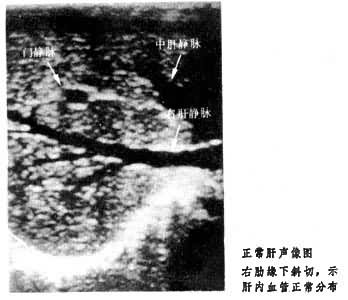

多探头阵列技术中,探头可以布成面阵,也可以是线阵。目前最常用的是线阵探头,即由多个换能器片排列成一直线,用电子开关技术使这些换能晶片依次通断,就可不必移动换能器而得到实时的B扫查声像了。同理,用面阵就可不需机械扫描而直接显示实时的 C扫声像。下面照片是用B型线阵超声诊断仪所摄得的肝声像图。

多探头阵列声成像技术,还为采用各种信息处理带来方便。例如:采用相控技术,就可以获得声束的所谓电子扫描;采用可变孔径和电子动态聚焦技术,可以在整个探测深度上减小声束宽度,提高声成像的横向分辨能力;采用灰阶显示可以提高图像的对比度;利用计算机技术可以抑制假信号,使声像图更为清晰,甚至还进行了把两套二维成像合成一个三维立体像的尝试。